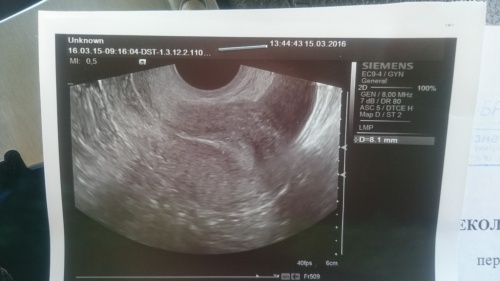

Нашли ЖТ - 20,4 на 22,1 мм, эндик - 8 мм.

Но УЗИстка была не в настроении явно и сказала, что ничего хорошего не видит и ЖТ у меня хиленькое, и кровоток плохой, явно гормонов каких то не хватает. Сказала, что ЖТ наверное давно, по этому такое (хотя О точно на 20 дц - не раньше), и дальше пойдет только на убыль(((